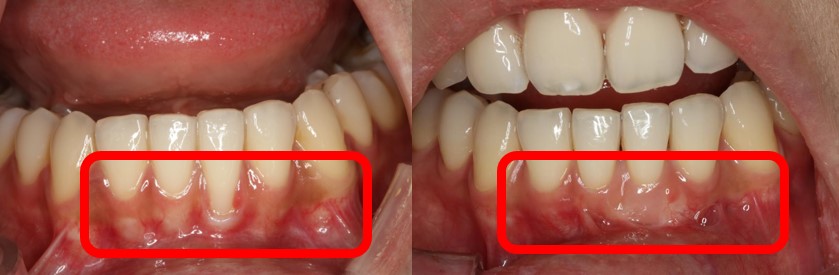

치주질환 및 정출로 인해 잇몸이 퇴축되고 치아 뿌리가 상당 부분 노출된 환자의 모습

김윤정 관악서울대치과병원 교수(치주과 전문의)는 “지나치게 단단한 칫솔모를 사용해 과도한 잇솔질을 하는 것, 이갈이 등의 악습관도 잇몸 퇴축을 촉진할 수 있다”라며, “이밖에도 치아 뿌리의 만곡도나 치아가 배열돼있는 포물선 형태인 ‘악궁’ 내 치아의 위치도 영향을 줄 수 있고, 맞닿는 대합치가 없어 치아가 솟아나는 ‘정출’현상이 생기는 경우에도 상대적인 잇몸퇴축이 발생한다”라고 말했다.

잇몸병(치주질환)으로 인한 잇몸 조직의 소실은 주로 중장년층이나 노년층에서 나타나지만, 치아의 외상 등에 의해 치주조직이 얇은 부위에서 발생하는 치은퇴축은 젊은 연령에도 자주 발생한다.